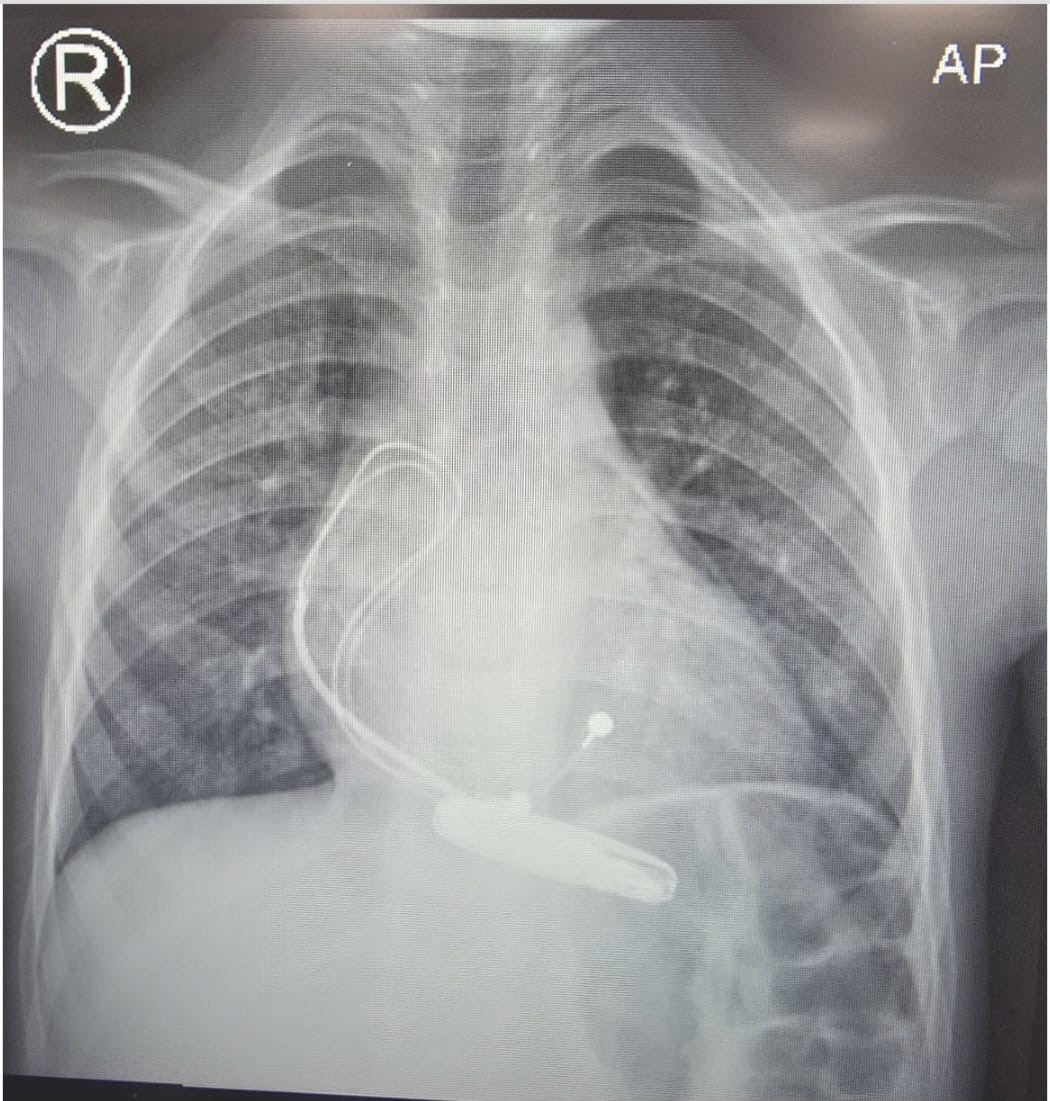

Post-procedural chest radiography confirmed appropriate pacemaker lead position and generator placement.

Figure 3: Post-pacemaker chest X-ray (AP view) showing appropriate lead positioning without complications.